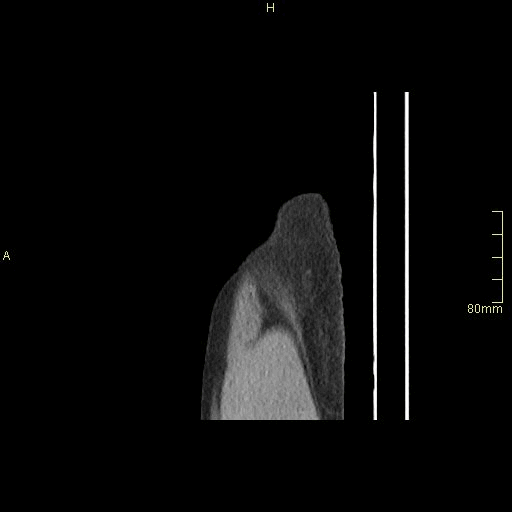

CT Pelvis (Portal Venous Sagittal)